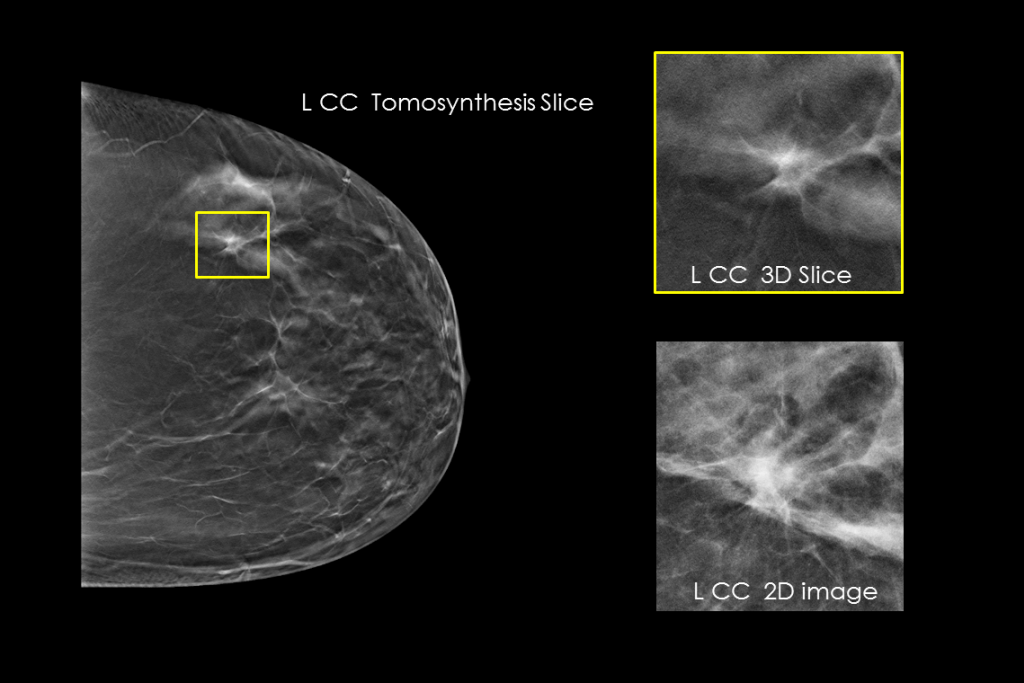

Clinical images of breast scan with suspicious Lesion